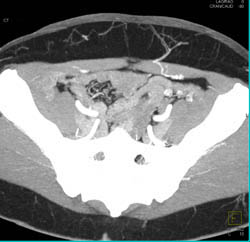

Tibial Plateau Fracture